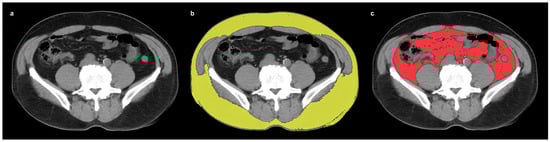

2.2. Measurements of CT-Attenuation of Adipose Tissue